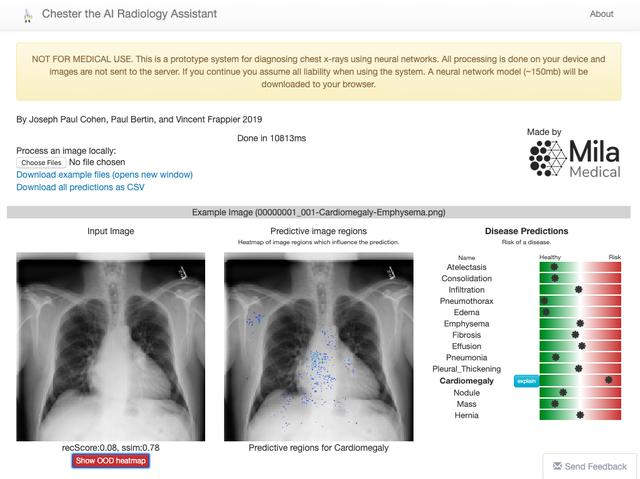

另一项工作是Chester,论文:https://arxiv.org/pdf/1901.11210.pdf,由蒙特利尔大学的研究人员开发。Chester是一个免费且简单的原型,医疗专业人员可以使用它们来了解深度学习工具的实际情况,以帮助诊断胸部X光。该系统被设计为辅助工具,用户可在其中处理图像以确认或协助诊断。

当前版本的 Chester(2.0)使用DenseNet-121型卷积网络训练了超过10.6万张图像。该网络应用程序未检测到Covid-19,这是研究人员对应用程序未来版本的目标之一。下面是诊断结果之一的截图(使用了Covid-19数据集的图像)

在下面的链接中,你可以访问Chester,甚至下载应用程序供脱机使用:https://mlmed.org/tools/xray/。